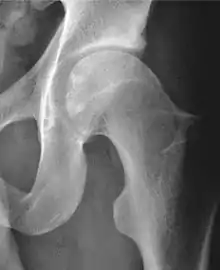

X-ray

Projectional radiography ("X-ray")is often considered first line for FAI.[10] Anterior-posterior pelvis and a lateral image of the hip in question should be attained.[10] A 45-degree Dunn view is also recommended.[10][19]

| Alpha angle | ![]() |

Degree of bulging of the femoral head-neck junction: In normal conditions there is a symmetric concave contour at the junction of the femoral head and neck. Loss of this concavity or bone bulging may lead to cam type impingement. The degree of this deformity can be measured by the alpha angle. Although it can be measured in the cross-lateral view, the 45° Dunn view is considered more sensitive and the frog leg view more specific in determining pathologic values. |

|